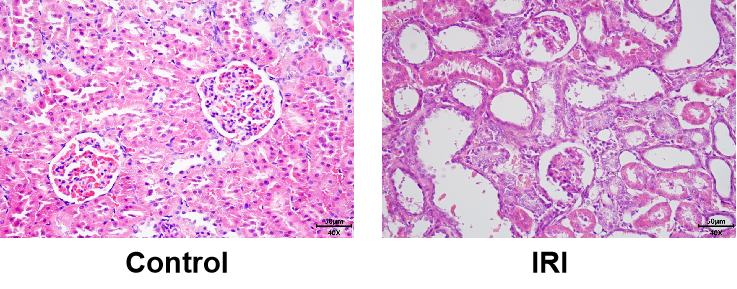

关键词:肾缺血再灌注、IRI、Renal ischemia reperfusion injury

造模方法:暴露双肾及肾蒂,游离双肾蒂,以血管夹钳夹双侧肾蒂,阻断 45min后松开左侧血管夹使双侧肾脏重新获得灌注。

急性肾损伤(acute kidney injury,AKI)是临床上较为常见的急危重病症之一,常见于大手术后、创(烧)伤、危重病等患者中,可导致患者电解质紊乱、酸中毒及容量负荷过重,并最终可发展成为尿毒症。肾缺血再灌注(renal ischemiareperfusion,RIR)损伤是由各种原因导致的肾脏灌注不足所致,伴随着一系列连贯的细胞事件发生,包括活性氧 (ROS) 释放、凋亡、坏死、炎症细胞的浸润和活性介质的释放,从而导致组织损伤,常见于各种类型的休克、急性肾动脉阻断或肾脏移植等临床